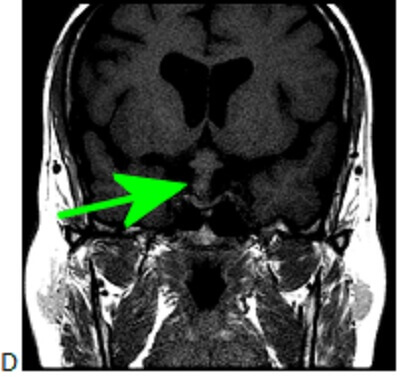

Figure 1B-D: The mass is very T2 hyperintense (B) with a dependent nodule of lower T2 hyperinstensity (blue arrow). Coronal T1 post contrast (C) and pre contrast (D) demonstrate subtle nodular enhancement along the inferolateral margin of the mass (green arrow).